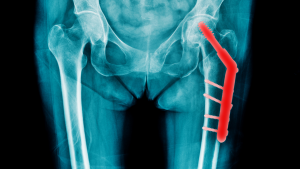

Ein Implantat ersetzt Stabilität – Prävention wäre besser gewesen.

Nebenbei bemerkt: Die Lebensqualität von Menschen, die einmal an der Hüfte operiert wurden, ist oft massiv eingeschränkt. Da will wirklich niemand freiwillig hin.

Beidseitige Hüftprothesen – ein drastisches Ergebnis eines vermeidbaren Risikos.